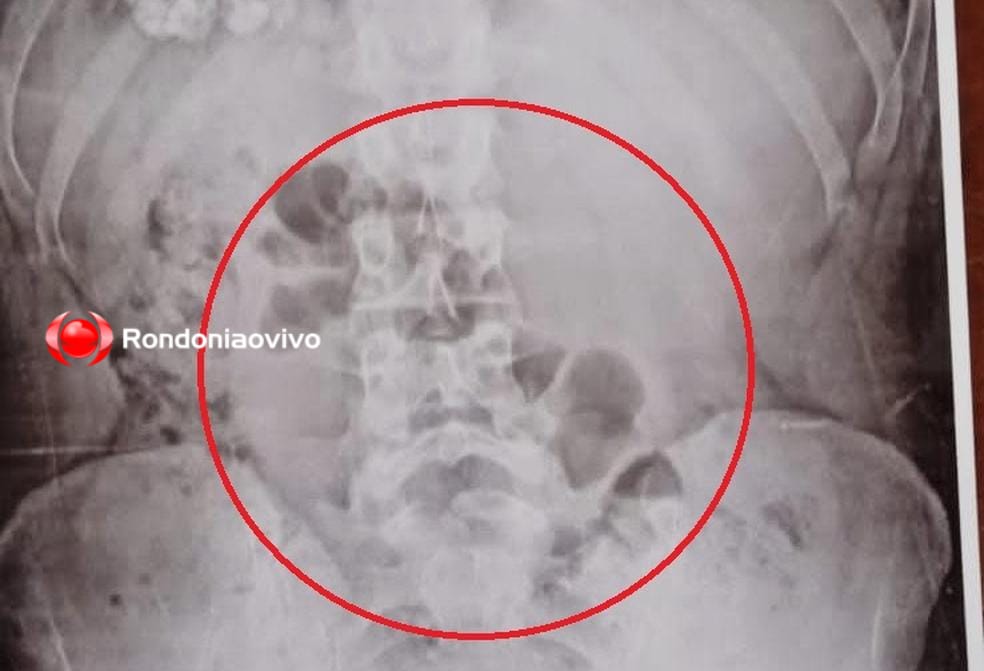

Mulher foi descoberta com a droga no estômago durante revista através do equipamento de raio-X

Traficante foi levado ao Departamento de Flagrantes